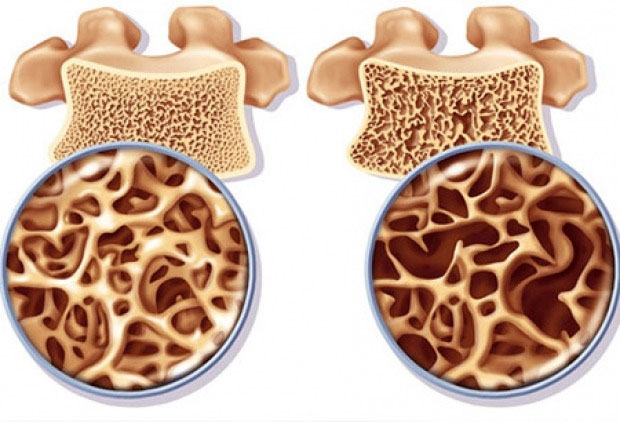

برای آنکه متوجه شویم پوکی استخوان چگونه اتفاق میافتد، باید فیزیولوژی استخوان را به صورت خلاصه بررسی میکنیم. استخوان یک بافت زنده و دائما در حال تغییر است که از یک لایه داخلی و یک لایه خارجی تشکیل میشود. لایه خارجی نازک و متراکم است و لایه داخلی دارای ساختار خانه-خانه و مشابه کندوی زنبور عسل است. بافت استخوان از فیبرهای پروتئینی مستحکم و با خاصیت الاستیکی به نام کلاژن، فسفات کلسیم و مواد معدنی دیگر تشکیل میشود. ترکیب شبکه کلاژن و فسفات کلسیم باعث استحکام و در عین حال انعطافپذیری در برابر ضربات میشود.

زمانی که حفرههای میان شبکهها در لایه داخلی، به علت تحلیل کلسیم بزرگ میشوند، استخوان به تدریج خالی شده و پوکی استخوان اتفاق میافتد. بنابراین استخوان شما ضعیف شده و با کوچکترین ضربهای دچار شکستگی میشود. از دست رفتن تراکم استخوانها به طور خاموش و بی سروصدا اتفاق میافتد و اغلب مواقع نیز هیچ علامتی تا زمان شکستگی ندارد.